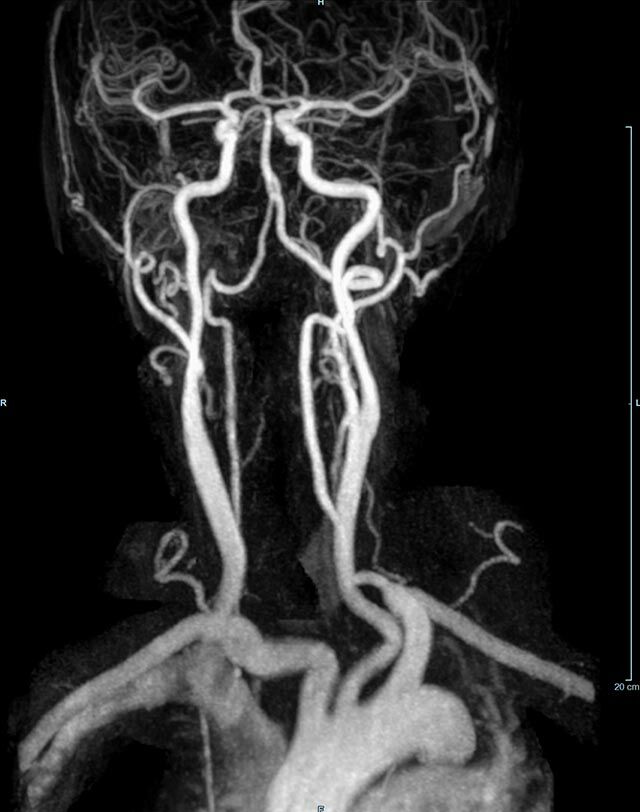

Kopf/Hals

Kopf

• akute Schlaganfalldiagnostik und chronische Durchblutungsstörungen

• entzündliche Prozesse des Gehirns oder der Gesichtsweichteile

• Tumore, ggf. mit Spektroskopie

• Abklärung Schwindel, zentrale Sehstörung, Kopfschmerz

• Metastasenverdacht

Halsgefäße

• Multiple Sklerose

• Abklärung Hirnnerven, Schädelbasis inkl. Hypophyse

• Abklärung Kleinhirn, Hirnstamm, Halsmark

• intrakranielle Gefäße (Abklärung Verschluss, Stenose, Aneurysma)

• Halsgefäße zur Therapieplanung (z.B. Stent, Operation)